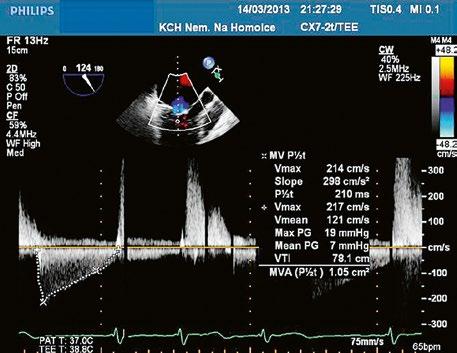

Plastika malformované mitrální chlopně u AVSD může být velmi obtížná, hrozí riziko mitrální stenózy (Obr. 45.23, Video 45.19, Video 45.20, Video 45.21), v některých případech je nutná náhrada mechanickou protézou. Při těžké trikuspidální regurgitaci je indikována i plastika trikuspidální chlopně, při dokumentovaných supraventrikulárních arytmiích MAZE výkon.

Při SAS je nutná resekce abnormálních šlašinek v LVOT. Pacienty s AVSD má operovat chirurg se zkušenostmi s VSV („kongenitální chirurg“).

Obr. 45.23 Dopplerovský záznam mitrálního průtoku z TEE u pacienta po uzávěru inkompletního AVSD a plastice mitrální chlopně v dětství s reziduální kombinovanou mitrální vadou, mitrální stenózou a regurgitací ( Video 45.19, Video 45.20, Video 45.21)